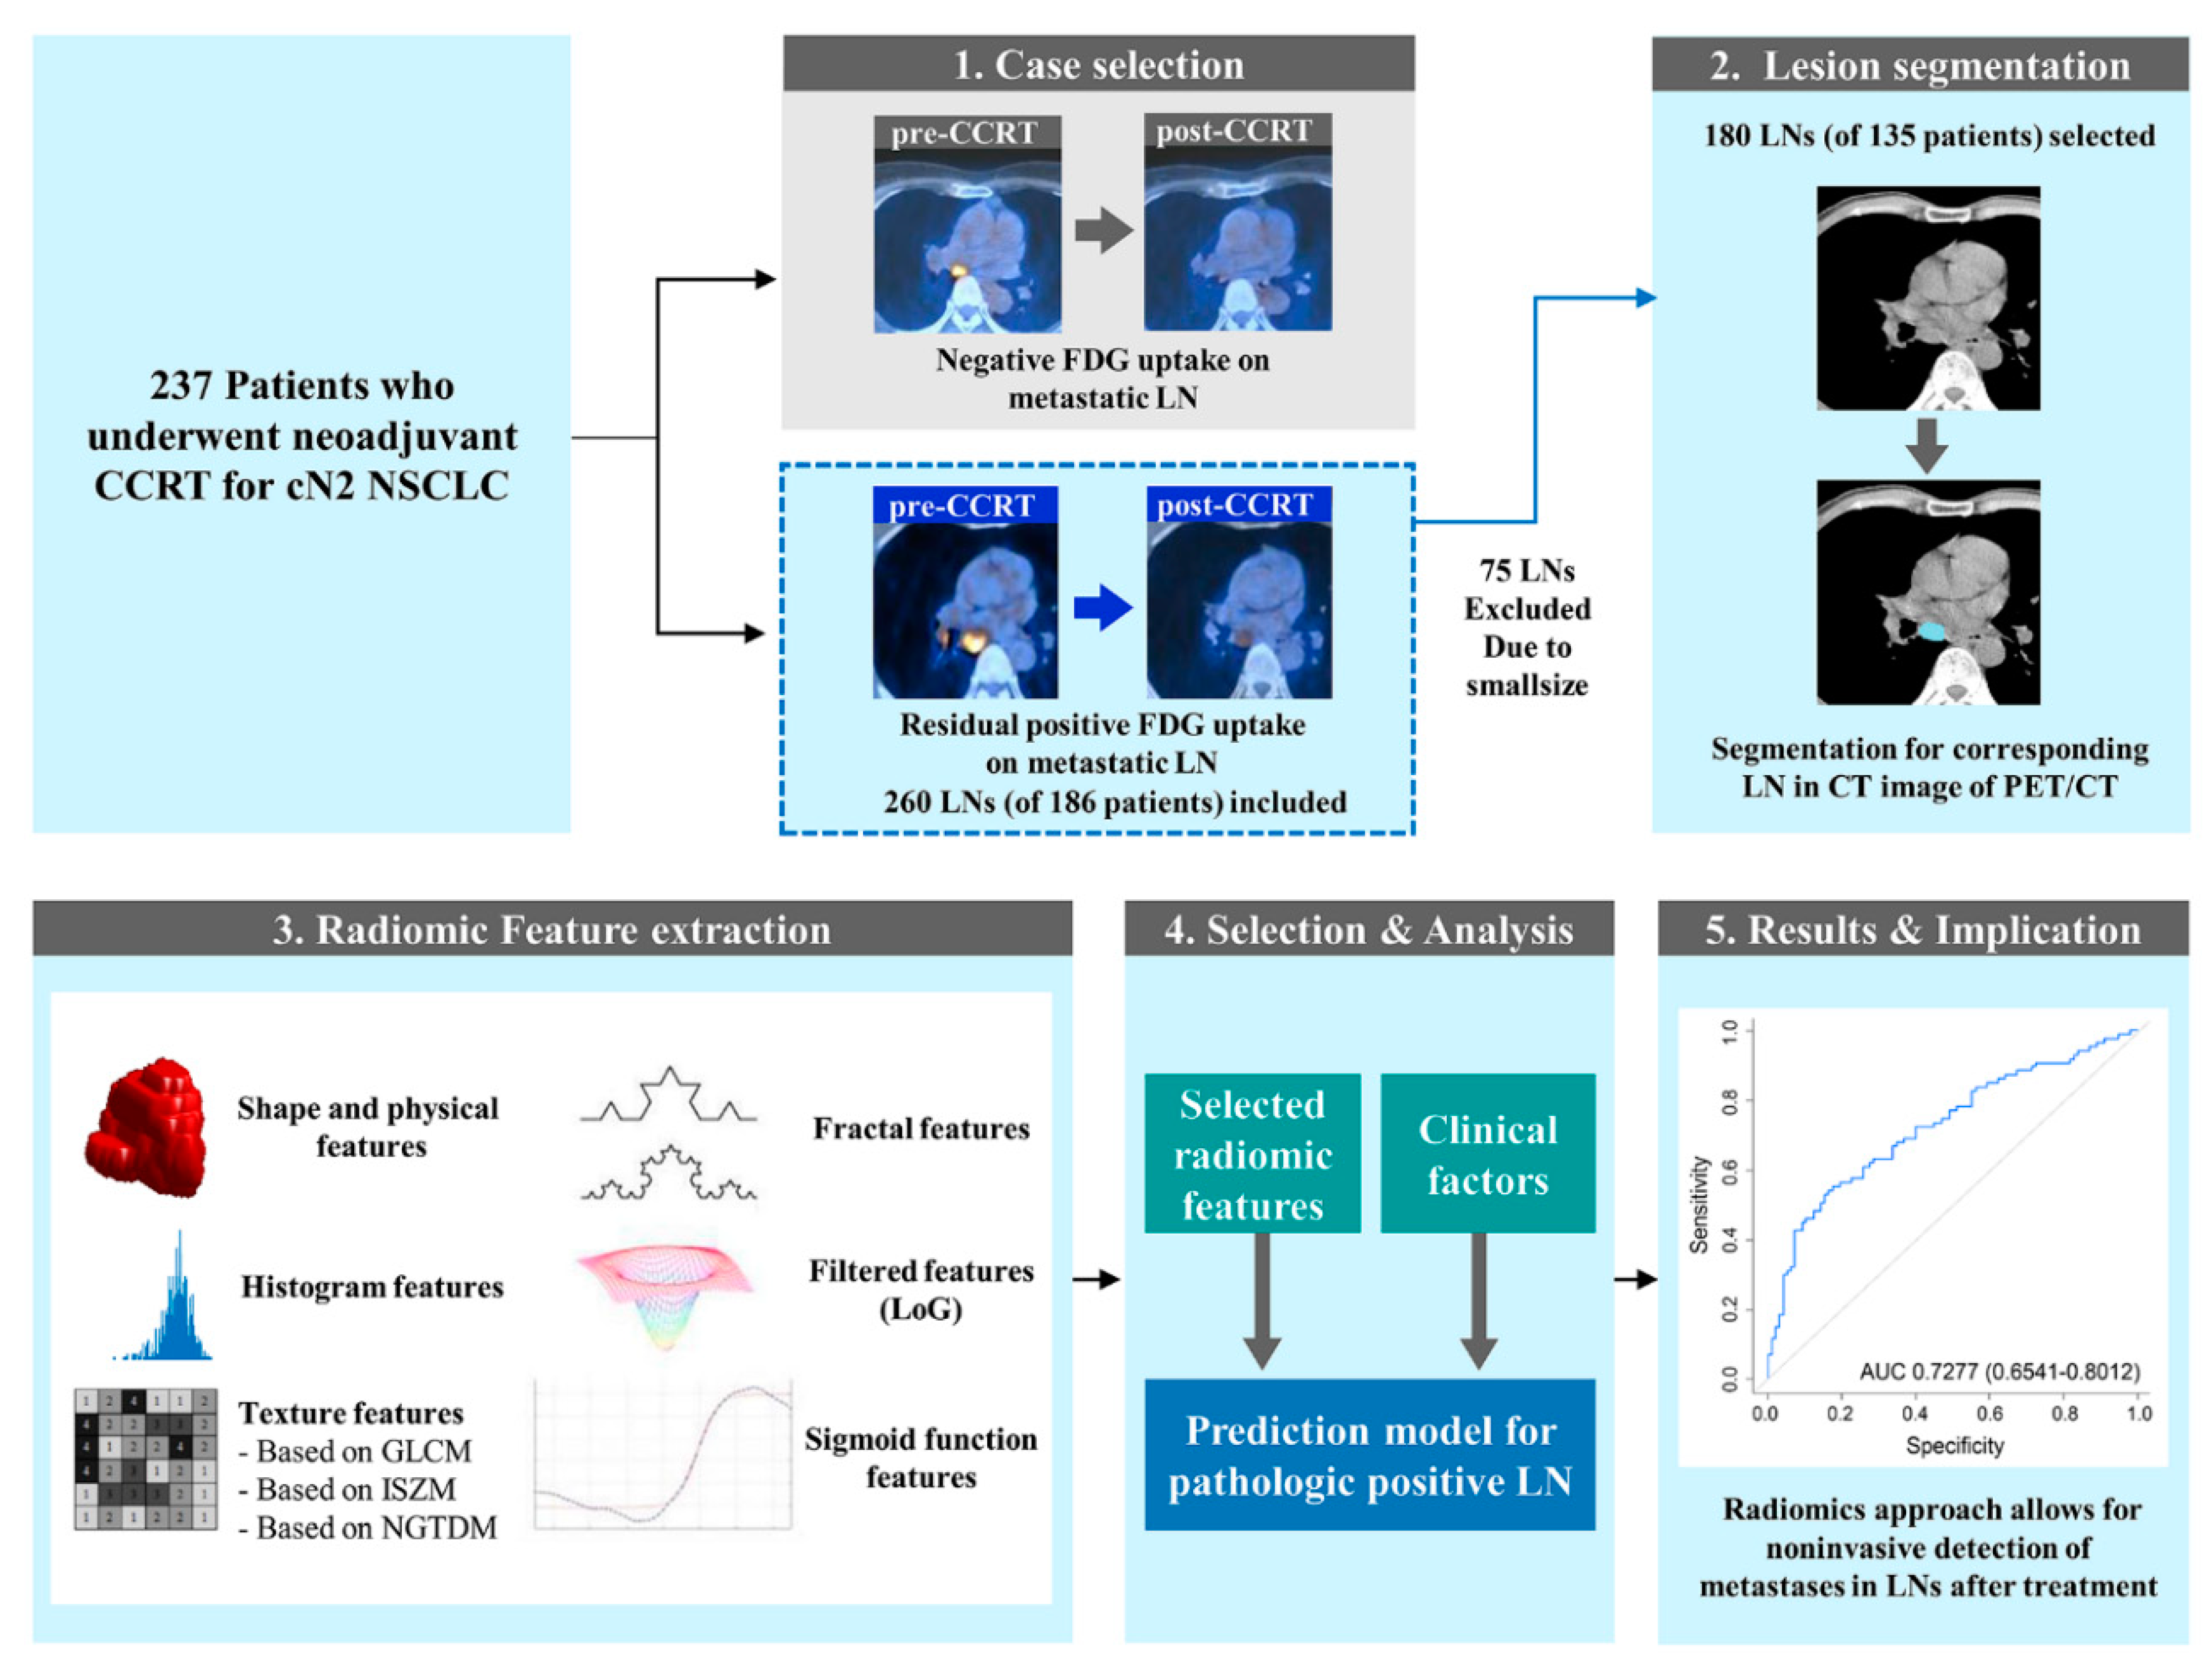

4. Materials and Methods

4.1. Patients

4.2. Image Analysis and Region of Interest Segmentation

4.3. CT Radiomics Feature Extraction

4.4. Statistical Analyses